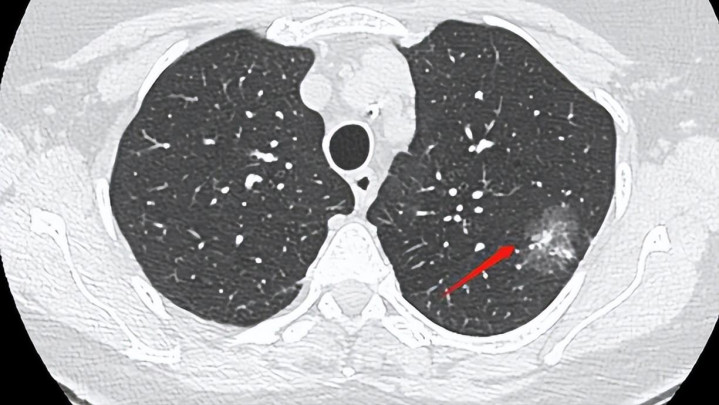

听起来惊人,但这背后并不代表疾病猖獗,而是机器更“聪明”、医生更“细心”了。一个9毫米的影子,可能是老感染后的纤维灶、吸入粉尘后的反应结节,甚至只是扫描角度的错觉。

所以,当那位女士被告知查出结节,她并没慌乱。医生建议定期复查,看看这“白点”是稳着呢,还是“走形儿”了。半年后复查,她的结节——没了。

所谓消失,其实并不神秘。有的结节本身是炎症反应,随着身体免疫修复,它自然会被吸收。也有的结节,在影像学上被后期判定为重叠结构或假像,第二次CT时角度一变,看不到了。

所以医生常说,别在第一次报告上打结。结节到底是什么,需要时间的观察、对比的分析。每三到六个月复查一次,连续两年如果不变形、不增大,那就是稳定的“老人”。